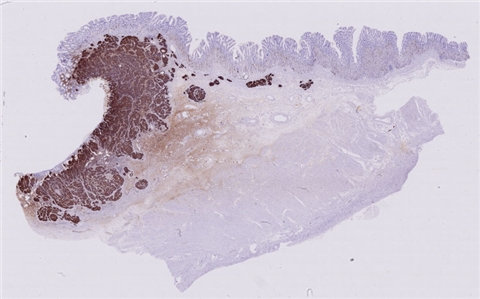

患者详情: 患者于半年前无明显诱因出现大便带血,为暗红色血便,未见粘液脓血便,反复发作,无腹痛腹胀,伴大便次数增多,并大便不成形,逐渐变细,初未引起重视,亦未行相应治疗,后症状逐渐加重。为进一步诊治,2020年3月入住我院。 直肠指诊:括约肌紧张度:正常,狭窄:无,触痛:无,距离肛门口大约4cm可及一环直肠一周肿块,质硬,移动度差,无压痛,指尖稍可通过肿块,指套染血:有。 电子肠镜示:距肛门4cm直肠处可见一巨大新生物,中间凹陷,底覆污秽苔,环2/3腔生长,钳取6块送病理,余 结肠各段粘膜光整,血管纹理清晰,未见明显的溃疡、息肉。 活检病理示:恶性肿瘤。后行腹腔镜直肠癌根治术。

大体所见: 1、直肠癌肿物:已切开肠管一段,长10cm,一侧切缘周长4cm,另一侧切缘已缝合,长3cm,紧邻缝合切缘见一溃疡型肿物,大小4.5*4*3cm,肿物切面灰白灰黄色、质硬,与周围组织分界欠清,侵及全层。

2、上切缘:灰褐色黏膜组织一块,大小1*1*0.4cm。

3、下切缘:灰褐色黏膜组织一块,大小1.2*1*0.4cm。

免疫组化: 2002032-004#:CgA(弱+)、syn(+)、CD56(+)、 2002032-002#:CK(+)、TTF-1(+)、CD34 +、SMA(-)